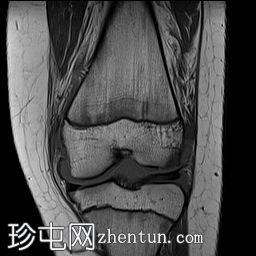

冠状位

T1加权像

冠状位PD序列

脂肪抑制序列

关节内大量积血,可见血细胞比容增高征。股骨外侧髁前部及髌骨内侧可见挫伤性微骨折。髌骨内侧支持带及髌股内侧韧带水肿增厚。髌骨内侧关节面下关节软骨浸润,提示I期骨软骨损伤。

髌骨外侧隐窝可见游离体,其信号强度与关节软骨一致,提示髌骨关节软骨外剥离损伤。股骨滑车和股骨关节软骨正常。

胫骨近端和腓骨骨骺以及股骨远端延伸至干骺端的骨骺周围可见局灶性骨髓水肿。这些提示存在局灶性骨骺周围水肿区。

十字韧带和侧副韧带正常。半月板正常。股四头肌腱和髌腱正常。

该病例具有短暂性髌骨外侧脱位复位损伤的特征性表现,包括预期的骨挫伤模式、内侧髌骨支持带/内侧髌股韧带损伤、髌骨骨软骨损伤以及髌骨软骨游离体。